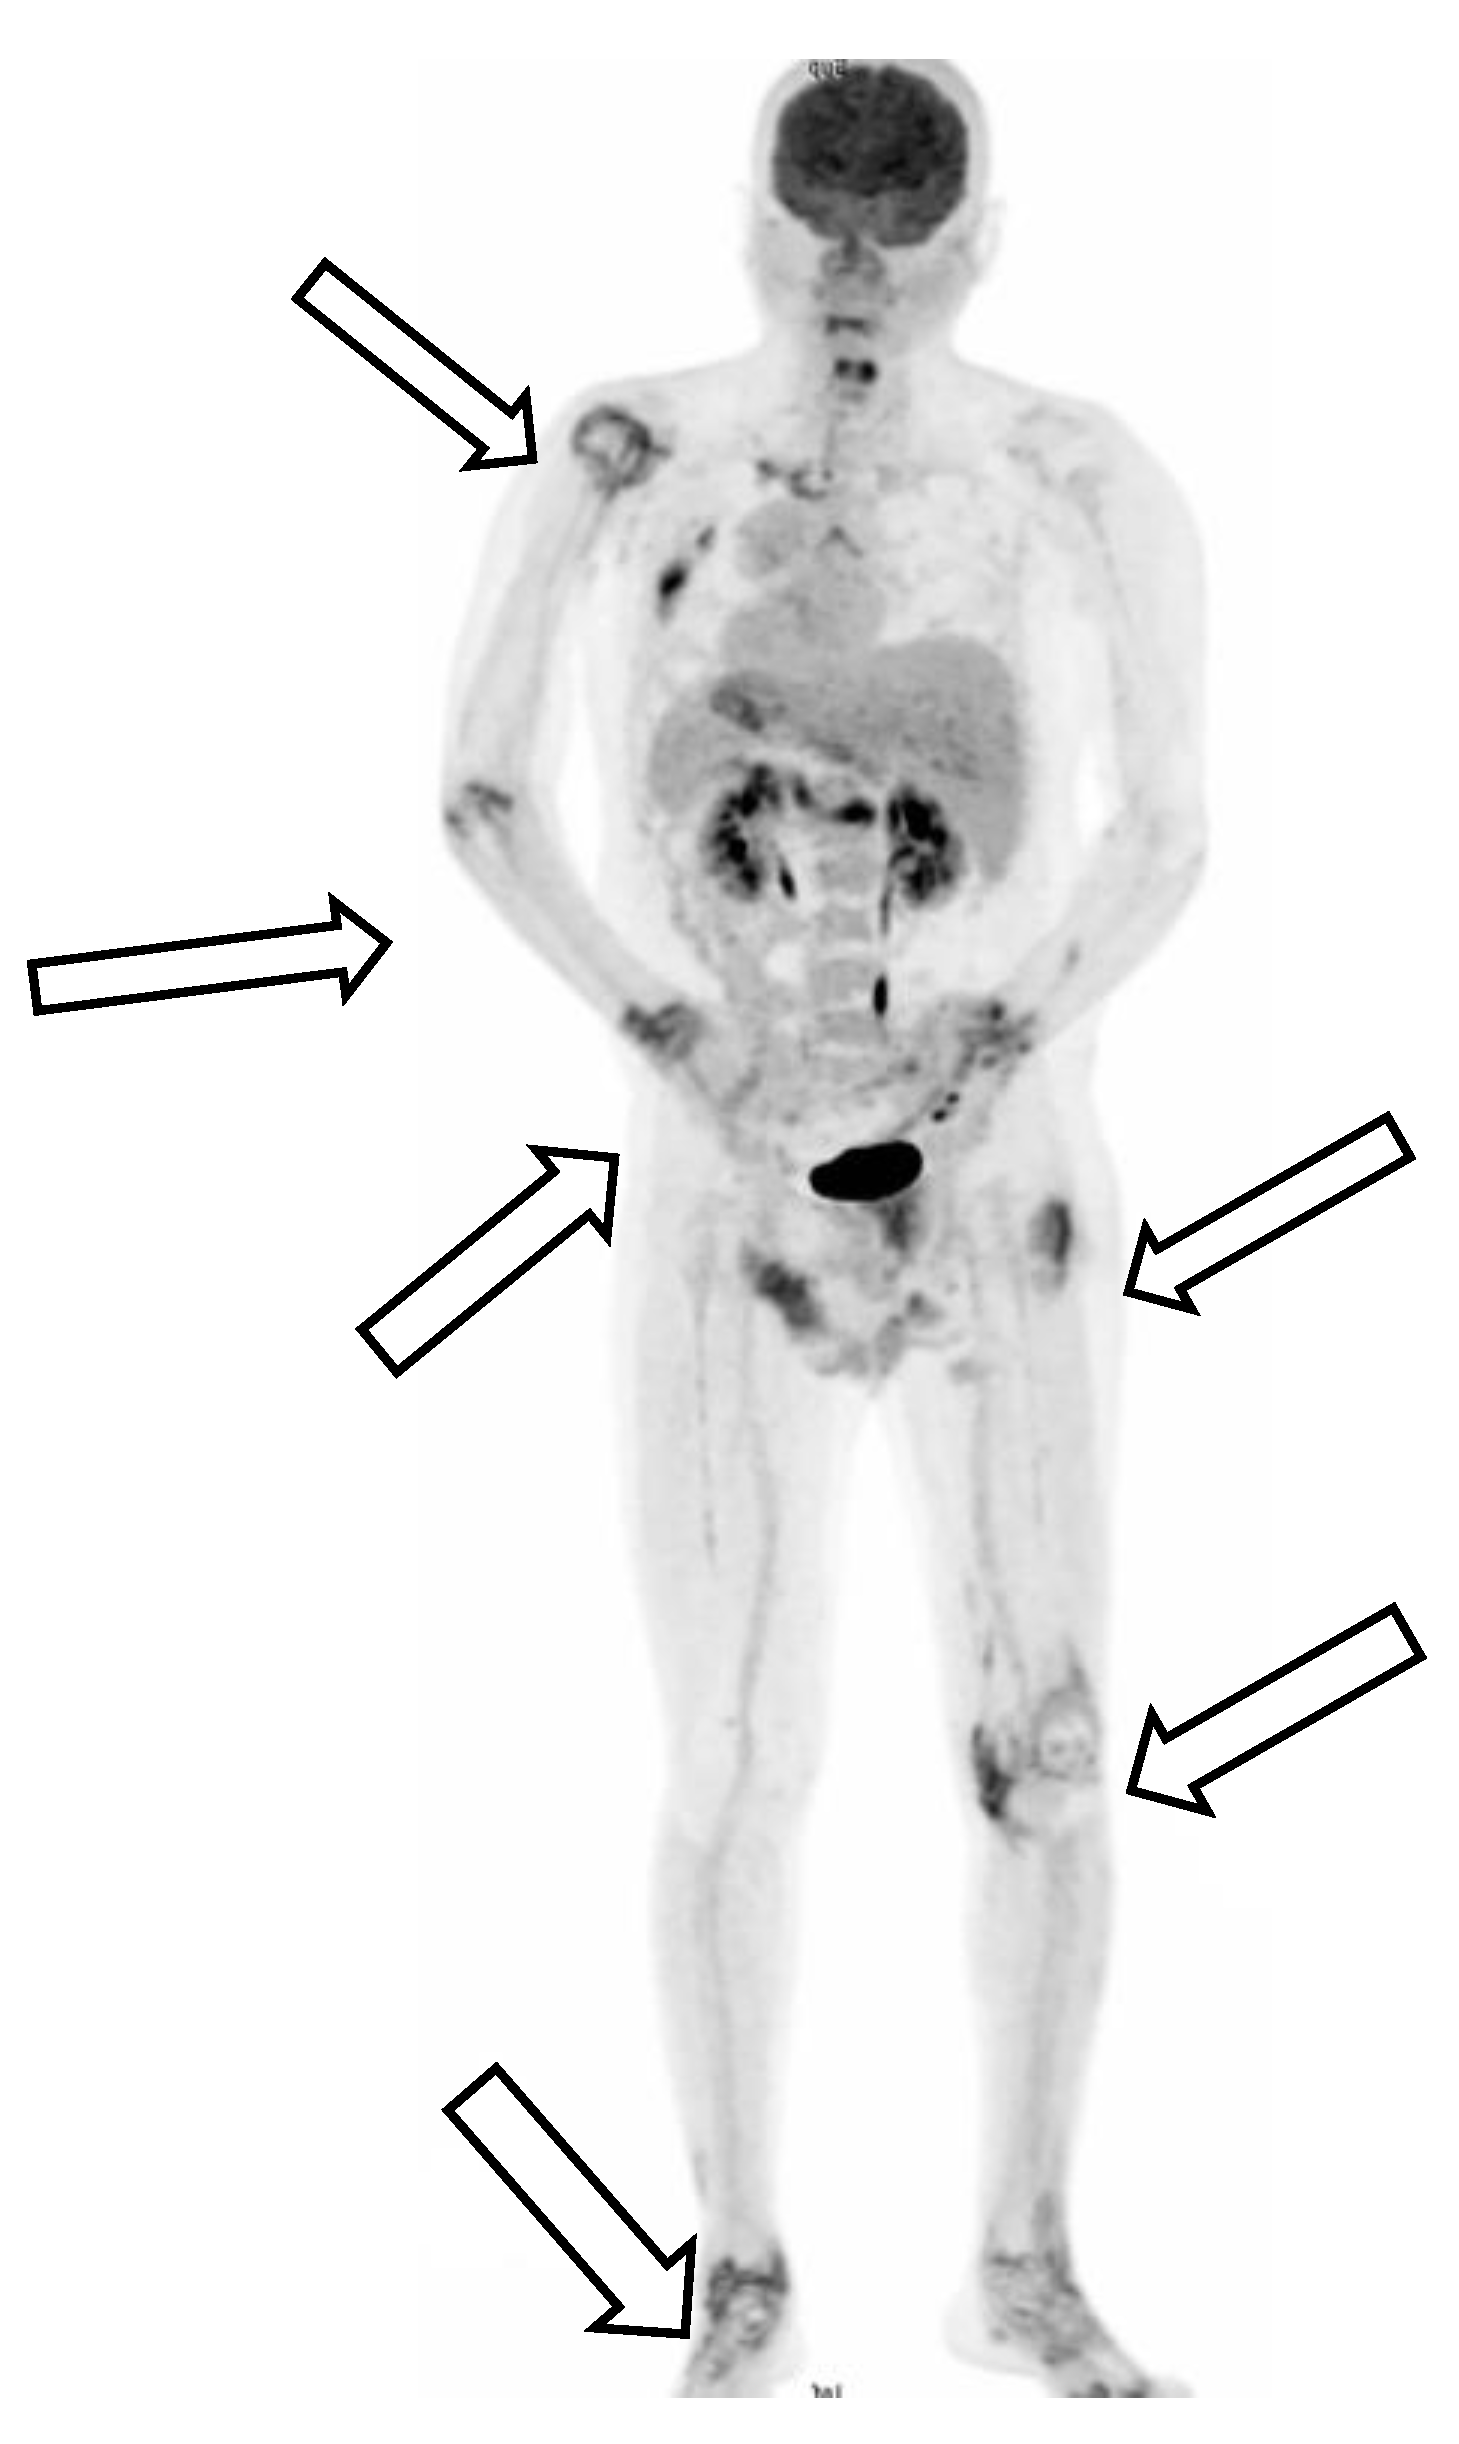

However, polyarthritis in both wrists, metacarpophalangeal joints, knee joints, and ankles developed one week after the patient’s first discharge from the hospital. Physical examinations on the second admission revealed an alert consciousness without abnormal neurologic reflexes. A gallium-67 tumor scan indicated inflammation in the left shoulder, left sternoclavicular junction, left interscapular region, lateral right hip region, left buttock, right knee, and left ankle, but no evidence of malignancy (Figure 2).

Figure 2. A gallium-67 tumor scan indicated inflammation over left shoulder, left sternoclavicular junction, left interscapular region, lateral right hip region, left buttock, right knee, and left ankle, but no evidence of malignancy.